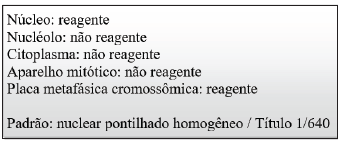

Interprete o seguinte resultado de FAN em

células HEp-2 por IFI:

De acordo com essas informações, o autoanticorpo associado com esse padrão de FAN é o:

De acordo com essas informações, o autoanticorpo associado com esse padrão de FAN é o: